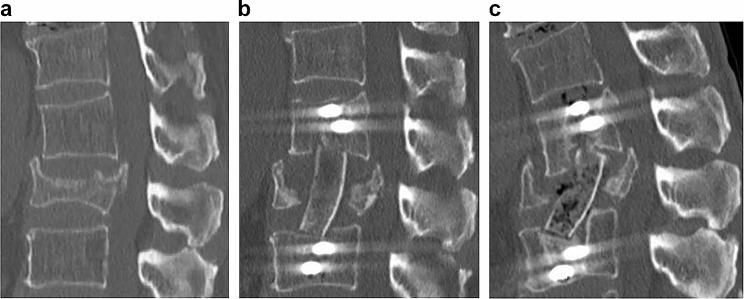

To achieve good bone fusion in anterior column reconstruction for vertebral fractures, not only bone mineral density (BMD) and bone metabolism markers but also lever arms due to bone bridging between vertebral bodies should be evaluated. However, until now, no lever arm index has been devised. Therefore, we believe that the maximum number of vertebral bodies that are bony and cross-linked with the contiguous adjacent vertebrae (maxVB) can be used as a measure for lever arms. The purpose of this study is to investigate the surgical outcomes of anterior column reconstruction for spinal fractures and to determine the effect of bone bridging between vertebral bodies on the rate of bone fusion using the maxVB as an indicator of the length of the lever arm.

The clinical data of 81 patients who underwent anterior column reconstruction for spinal fracture between 2014 and 2022 were evaluated. The bone fusion rate, back pain score, between the maxVB = 0 and the maxVB ≥ 2 patients were adjusted for confounding factors (age, smoking history, diabetes mellitus history, BMD, osteoporosis drugs, surgical technique, number of fixed vertebrae, materials used for the anterior props, etc.) and analysed with multivariate or multiple regression analyses. The bone healing rate and incidence of postoperative back pain were compared among the three groups (maxVB = 0, 2≦maxVB≦8, maxVB ≧ 9) and divided by the maxVB after adjusting for confounding factors.

Patients with a maxVB ≥ 2 had a significantly higher bone fusion rate (p < 0.01) and postoperative back pain score (p < 0.01) than those with a maxVB = 0. Among the three groups, the bone fusion rate and back pain score were significantly higher in the 2≦maxVB≦8 group (p = 0.01, p < 0.01).

Examination of the maxVB as an indicator of the use of a lever arm is beneficial for anterior column reconstruction for vertebral fractures. Patients with no intervertebral bone bridging or a high number of bone bridges are in more need of measures to promote bone fusion than patients with a moderate number of bone bridges are.